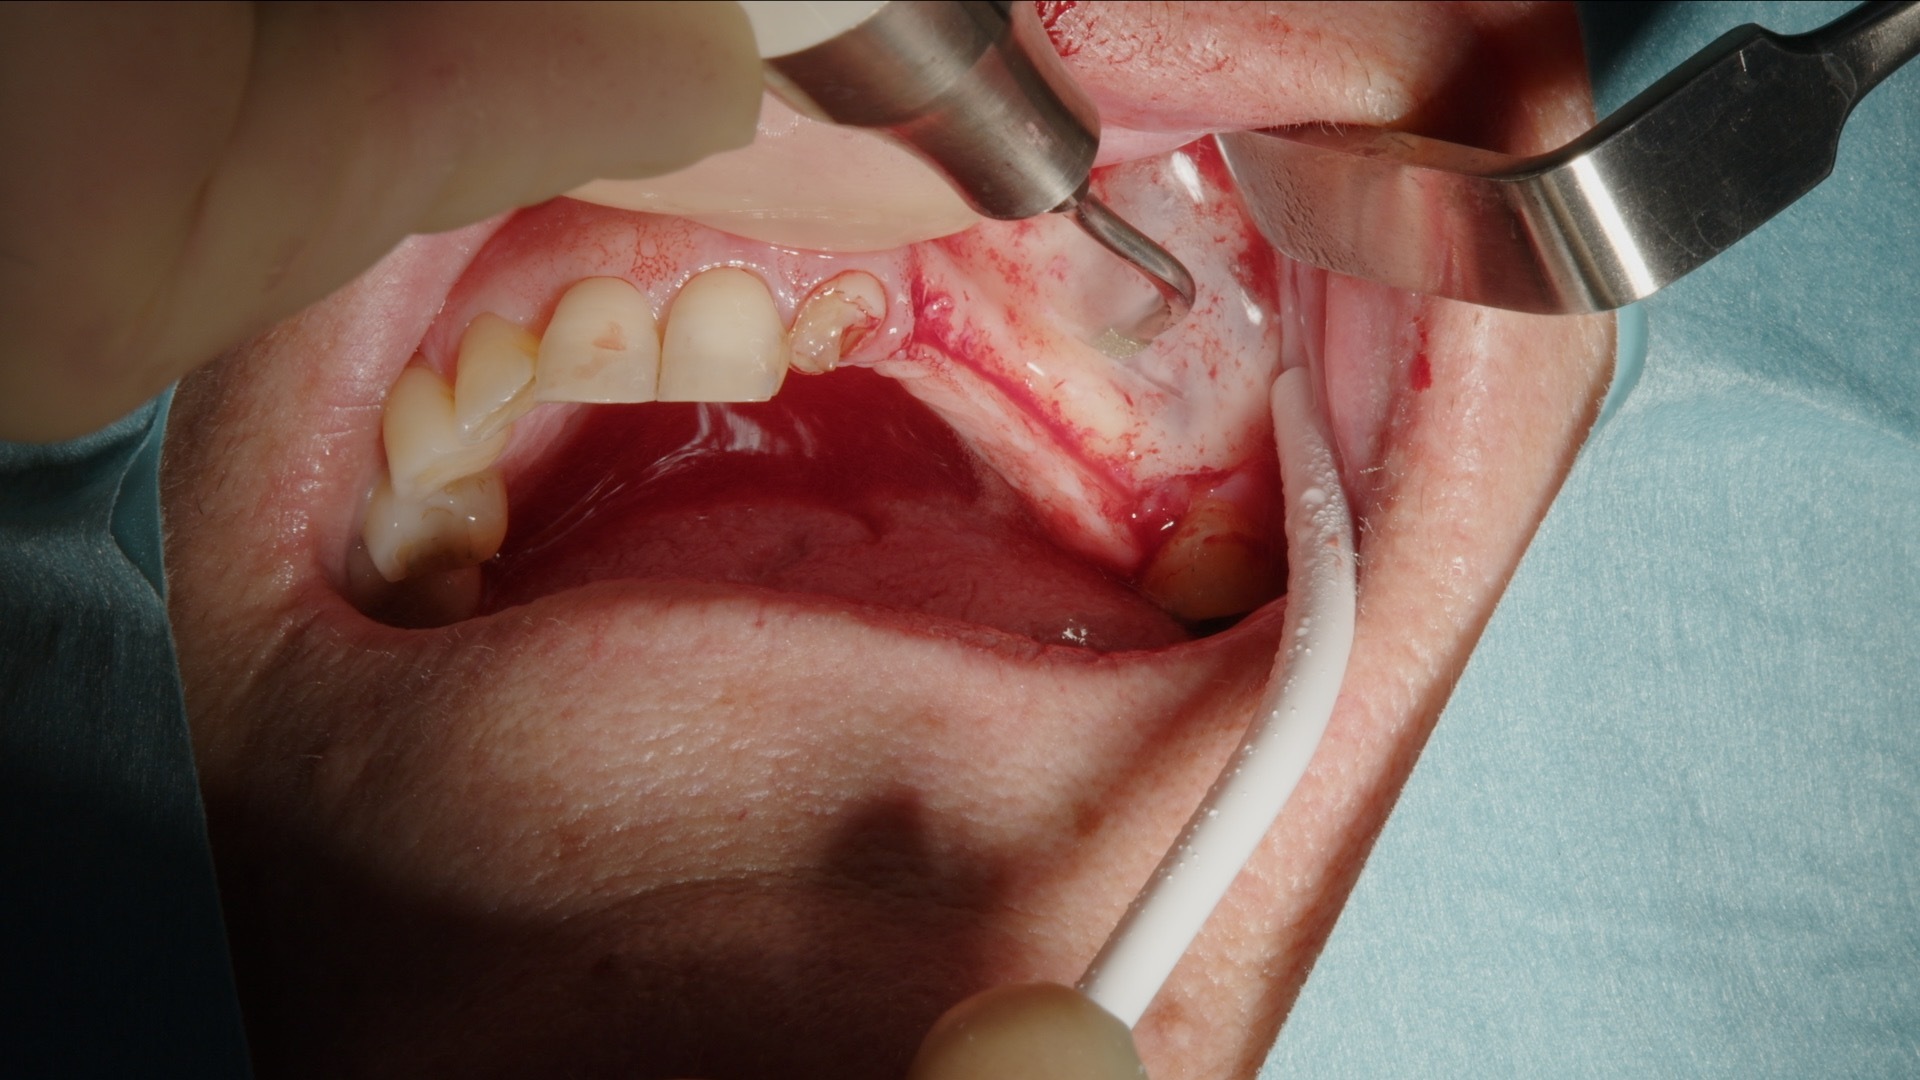

3. Skonsam elevation av sinusmembranet med piezo-lyftspets.

4. Fullt preparerat lateralt fönster inför augmentation.

För elevation av Schneiderianska membranet används dedikerade piezospetsar, vilket möjliggör en skonsam och kontrollerad separation med god visuell överblick.